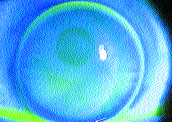

FIG. 1: Fluorescein shot of an RGP lens on a keratoconus eye, taken via a digital imaging system.

FIG. 2: Fluorescein shot of an RGP bifocal contact lens taken via a digital imaging system.